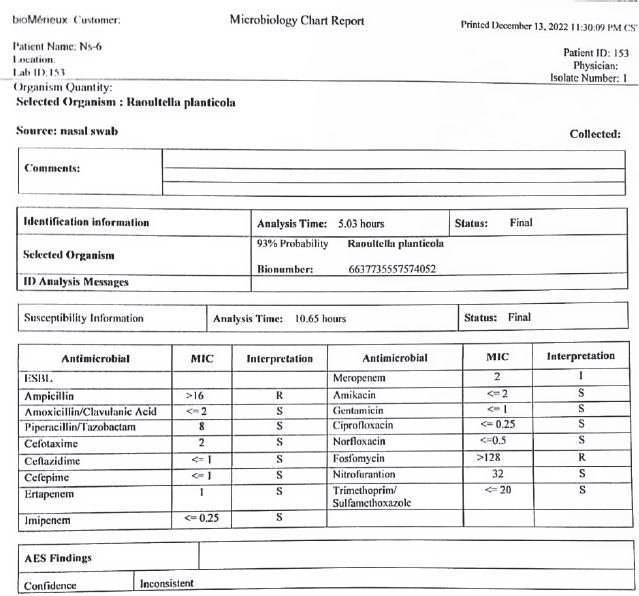

AbstractBackground: The bacteriological and histopathological study of Raoultella planticola in local rabbits is not presented in previous research. There is no specific information about studying this bacterium in local rabbits. Hypothesis: The present study was based on bacteriological and histopathological changes in the trachea and lungs of local rabbits, as the samples were collected from 50 unhealthy local rabbits that appeared to be suffering from respiratory signs. Aims: To study the bacteria that were isolated for the first time from sheep suffering from respiratory infections, and diagnose them through VITEk2. Methods: We injected the isolated bacteria into (50) group of local rabbits (Oryctolagus cuniculus) and studied the histopathological changes in the trachea and lungs. Due to their similar morphological characteristics, our investigation reported this bacterium as Gram-negative rods. Then used the VITEK2 system to confirm the species of bacteria (93% Probability). Results: The animals clinically showed results (dullness with nasal and ocular discharge and cough). Then, euthanasia was performed to sacrifice animals seven days post-infection. The trachea and lungs were used in a histopathological study using routine Hematoxylin and Eosin stained. In this study, emphysema and bronchitis are often grouped under the heading of chronic obstructive pulmonary disease (COPD). Conclusion: Raoultella planticola infections are uncertain, and further studies are required. The previous difficulties in the identification of R. planticola may be explained by the introduction of more detailed identification techniques, which are explained in the present study. The conclusion of this study also provides that Raoultella planticola causes mild to moderate emphysema in local rabbits. Keywords: Respiratory system, Oryctolagus cuniculus, Raoultella planticola, Parenchyma, Alveoli. IntroductionRaoultella planticola is a Gram-negative, non-motile, aerobic, encapsulated bacterium belonging to the Enterobacteriaceae family (Chun et al., 2014). In Iraq, local rabbits have a second small pair of upper incisors (Harcourt-Brown, 2002). The rabbits among the laboratory animals have been used as an experimental model for research (Ghoshal and Bal, 1989). It belongs to the genus Raoultella under the Enterobacteriaceae family. Two species are clinically important (Sahu et al., 2020). The microbiological identification of R. planticola remains a challenge even after 30 years of its identification (Howell and Fakhoury, 2017). The gastrointestinal tract and the upper respiratory tract are the typical reservoirs of R. planticola (Sękowska, 2017). Infections related to rare pathogens are very challenging to treat due to a lack of enough data in the medical literature (Sahu et al., 2020). These strains can act as a reservoir for these resistance genes (Demiray, et al., 2017). The lung is a soft, compact, and spongy mass of tissues lying in the pleural cavity within the thorax. Each lung is covered by a fold of coelomic epithelium formed of two layers, a layer which in contact with the organ (visceral pleura) and that lines the chest wall (parietal pleura). Between these two layers of pleura, there is a pleural space, which is a potential space containing a small amount of fluid. Each lung is divided into lobes (Ramchandi et al., 2001). Klebsiella pneumoniae is a type of gram-negative bacteria that is normally found in the human intestines without causing any disease. However, if it enters other systems of the body, it can cause different types of healthcare-associated infections, including pneumonia, bloodstream infections, wound or surgical site infections, and meningitis (Centers for Disease Control and Prevention 2010). This research aims to study the Raoultella planticola that were isolated for the first time from respiratory infections, then confirmation by the VITEK2 system, and study the morphological characteristic. Materials and MethodsSamples were collected from 50 animals that appeared suffering from respiratory signs, and in the laboratory used routine steps to the identification of bacteria culturing, gram stain, and urease test. After that, the VITEK2 system was used to confirmed the species of Raoultella planticola, VITEK2 system has two test depending on the kit that we used. The first is a test of the biochemical reaction of bacteria with a chemical substance, and the second is a test of the resistance of bacteria to antibiotics. The antibiotics profile will be mentioned later. After that, the isolated bacteria were diluted and injected into 5 local rabbits regardless of sex in the Miles and Misra method to get the minimal dose that can cause infection (5 animals used for control) in the current study. The rabbits were scarified under good health conditions and followed the appropriate instructions of the animal ethics of the University of Baghdad College of Veterinary Medicine in Iraq. Finally collected specimens for the histology study of the respiratory system, the trachea, bronchus, and lungs. Histopathological aspect of the studyThe first step after samples collection is fixation by formaldehyde 10% then dyhydration via ethanol (70%, 80%, 90%, and 100%) for 2 hrs each of step. After that xylen was used as a clearing agent for 2 hrs. Then the samples were impregnated in melted paraffin wax (55°C–58°C) for 2hrs. Each piece of sample was embedded in paraffin wax and finally cut into sections (5–6 µm thickness) by using the rotary microtome (Microtome Bright 5030). The sections were stained with haematoxylin and eosin for routine histology (Suvarna et al., 2019). All stained slides were examined under the light microscope and photographed with a digital camera (USB) connected to the computer, camera should adjusted, and setliy should be fixed throughout all steps of capturing with different magnification powers. The slides were captured directly from computer at various adjustment powers (x10, x40, x100, and x400) to evaluate the histopathological features. The examination and photograph were conducted at histopathology and microbiological Lab. College of Medicine/University of Fallujah. The histopathological and staining techniques that used were as following, Harris Hematoxylin and Eosin stain (H&E): This stain was used to detect the general features of the tissue (Luna, 1968; Suvarna et al., 2013). Ethical approvalThis study was conducted in conformity with the rules of the Animal Ethics Committee of the Faculty of Veterinary Medicine at the University of Kufa (license number: 27735 in 13/12/2022). ResultsBacteriological studyTo study the pathogenesis of Raoultella planticola through its natural route of infection (nasal route), an experimental infection was conducted using a dose of 159,000 CFU/mL. Ten healthy rabbits were divided into two subgroups: a control group (5 healthy animals) and an infected group (5 healthy animals inoculated intranasally with Raoultella planticola at a dilution of 10−3. The infected animals exhibited clinical signs, including dullness, nasal discharge, and ocular discharge. After seven days post-infection, the rabbits were euthanized, and post-mortem examination revealed pulmonary emphysema at the mentioned dose. Bacteriological analysis confirmed Raoultella planticola as Gram-negative rods. The VITEK2 system identified the species with a 93% probability, and 23 samples were positive. The isolates Raoultella planticola were then injected into local rabbits (regardless of sex) after dilution using the Miles and Misra method to determine the minimal infective dose (intranasal 10−3, 2.5 ml instillations). Antimicrobial susceptibility testingDisk diffusion susceptibility testing was performed following Bernal and Guzmán (1984) and Clinical and Laboratory Standards Institute (CLSI, 2023) guidelines. Fourteen antimicrobial agents were tested against Raoultella planticola: • Amikacin • Amoxicillin/Clavulanic acid • Cefixime • Ceftriaxone • Chloramphenicol • Ciprofloxacin • Gentamicin • Imipenem • Meropenem • Nitrofurantoin • Piperacillin • Streptomycin • Tetracycline • Trimethoprim The average inhibition zone diameters were recorded, and results were interpreted according to CLSI standards (Table 2). Table 2. VITEK2 result show susceptibility of Raoultella planticola.

The current study demonstrated that Raoultella planticola exhibits mild pathogenicity when administered via the intranasal route in rabbits. The observed clinical signs (dullness, nasal and ocular discharge) and pathological findings (pulmonary emphysema) suggest that this bacterium can induce respiratory infection under experimental conditions. These et al findings align with Podschun (1998), who reported that Raoultella planticola is an environmental bacterium commonly found in water, soil, and plants, capable of colonizing humans and animals. The bacterium is a facultative anaerobic Gram-negative bacillus belonging to the Enterobacteriaceae family. It forms mucoid colonies on MacConkey agar due to polysaccharide capsule production (Figs. 1 and 2), making it morphologically and biochemically similar to Klebsiella spp. (Table 1).

Fig. 2. A Comparison between Colonies of klebsiella pneumonia (A) culturing on MacConkey agar which appear as mucoid dark pink colony and Colonies of Raoultella planticola (B ) culturing on MacConkey agar appear as mucoid pink colonies Table 1. VITEK2 result show presence of Raoultella planticola.

The Vitek2 system provided reliable identification (93% probability), supporting the accuracy of the isolates used in this study. The antimicrobial susceptibility profile revealed varying resistance patterns, which may have clinical implications for treatment strategies. Further studies are needed to explore the virulence mechanisms and potential zoonotic risks associated with Raoultella planticola. Histopathological resultsHistological examination of lung tissue revealed emphysema and atelectasis (Fig. 6A and B). Emphysema was characterized by permanent enlargement of air spaces distal to the terminal bronchioles, accompanied by destruction of alveolar walls without significant fibrosis.